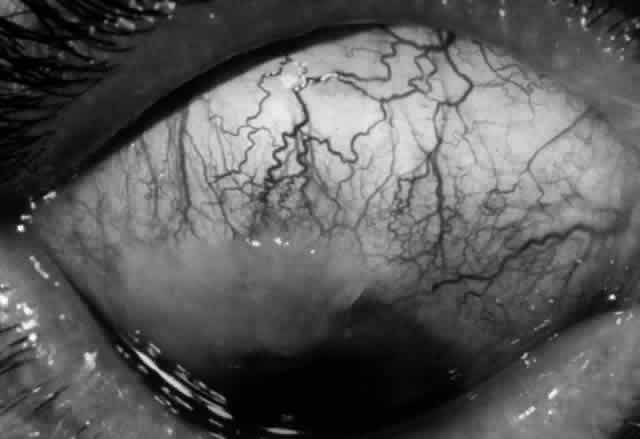

Clinically, the ocular disease in cicatricial pemphigoid (OCP) may present unilaterally in the form of a chronic, recurrent catarrhal conjunctivitis, but it eventually becomes bilateral. Subepithelial fibrosis is characteristic of stage 1 of OCP (Fig. 7). Stage 2 shows fornix foreshortening (Fig. 8), and symblepharon formation is the hallmark of stage 3 (Fig. 9). Stage 4, end-stage disease, is characterized by ankyloblepharon and surface keratinization (Fig. 10). Obstruction of the lacrimal ductules and meibomian gland ducts eventually produces an unstable tear film and progressive sicca syndrome, but it is to be emphasized that OCP is not a dry-eye syndrome until late in the disease course.20 Trichiasis and entropion occur because of the subepithelial fibrosis, with eventual keratopathy, corneal neovascularization, and corneal ulceration and scarring.20

Fig. 9. Stage 3 of an eye affected by cicatricial pemphigoid. The conjunctival “shrinkage” continued and a frank symblepharon developed.